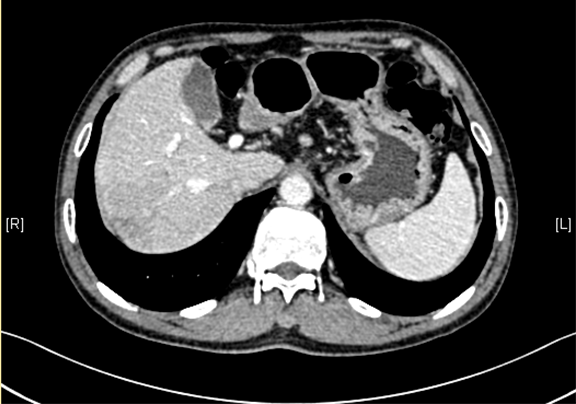

下腹部增强CT示:考虑肝右后叶肝Ca可能性大。肝顶异常强化灶,不除外不典型增生结节(DN)并癌变。肝硬化、脾大。

术前CT检查:

动脉期